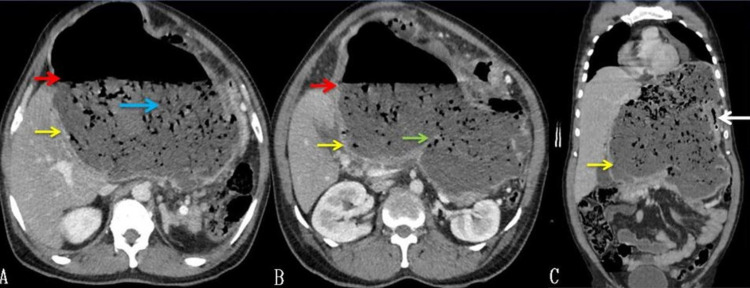

Routine blood investigations, including complete blood counts and renal function tests, were normal. A liver function test revealed mild elevation (174 IU/L) of alkaline phosphatase (ALP). Hydatid serology was positive. Abdominal USG showed the presence of a large hypoechoic cyst with air and debris. Contrast-enhanced CT of the abdomen showed a 20cm x 18cm cyst, arising from the left lobe of the liver having an air-fluid level and few septations or membranes at the inferior aspect of the cyst with debris. The left portal vein was compressed, and the left bile duct was not visualized. The gallbladder had air within it. The common bile duct (CBD) was normal in caliber, and there was no air within it (Figure 1).

Abdominal USG may show anechoic cyst, multiseptate cyst, floating membranes within the cyst, daughter cysts, and calcifications. If the cyst gets secondarily infected, it will lose its characteristic appearance [ref. 2]. Based on the USG appearance, these hydatid cysts have been classified by Gharbi et al. into five categories and WHO Informal Working Group on Echinococcosis (WHO-IWGE) into six categories [ref. 7,ref. 8]. The CT scan of the abdomen shows the location of the cyst, thickness of the wall, presence of daughter cysts, floating membranes, and calcifications if any. Both these imaging techniques usually will not be able to show any CBC if present. The presence of air within the cyst, which both imaging techniques can see, should be highly suggestive of the presence of cystoenteric fistula. In our patient, there was a large hypoechoic cyst with debris and air within it. CT showed debris in the dependent region with an air-fluid level with few membranes in the inferior aspect. The cyst had communication with the duodenum, and there was a presence of air within the gallbladder, with normal CBD without any air. We also hypothesize that the air in the gallbladder was due to duodenal fistulization of the cyst with preexisting CBC. Air must have entered in the biliary radicals and then into the gallbladder through the cystic duct.